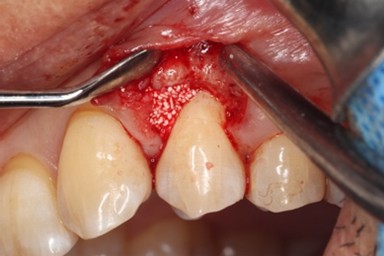

治療中

エムドゲイン®サイトランス®を填入し、レーザーにて血餅形成、縫合

歯周基本治療後に再評価し、ポケットが残存したのでEr:YAGレーザーを併用した歯周組織再生療法(エムドゲイン® 、サイトランス®を使用)を行ったケース

歯周病の好発部位である上顎第一小臼歯近心面における骨吸収に対して再生療法を行ったケース。一般的に根面溝という溝があり歯石の沈着が生じやすい。また溝の存在により術後に歯肉と歯根の付着が生じにくいため、今回はEr:YAGレーザーにて血餅形成を行い組織の安定化を図った。